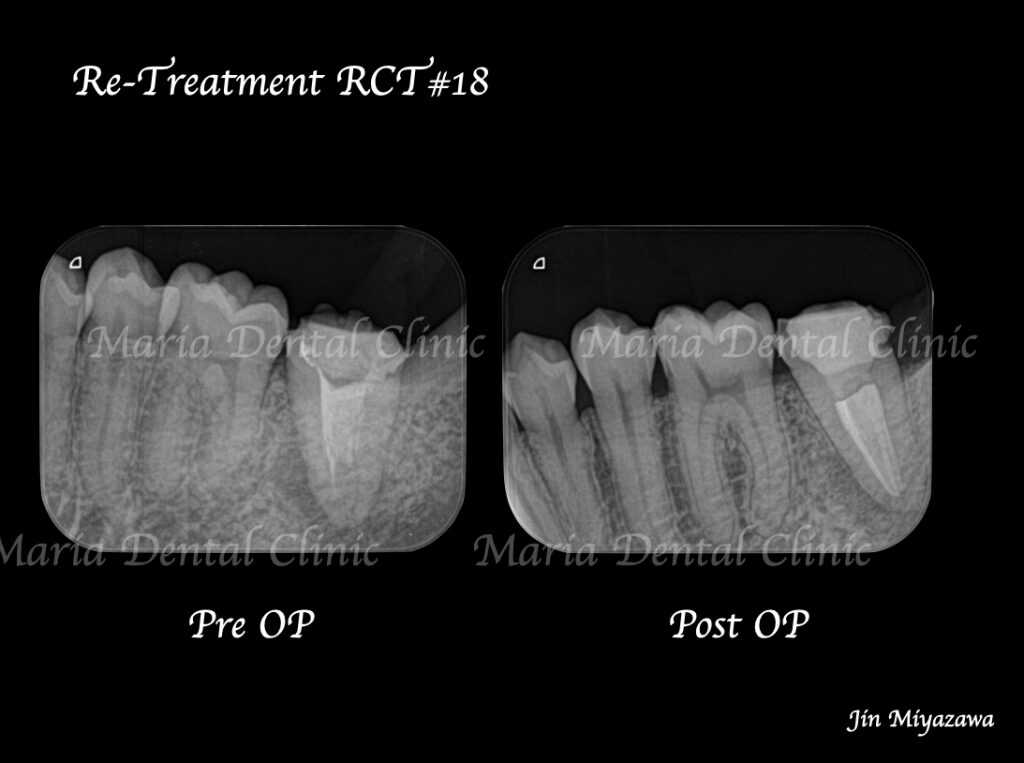

に対する、精密根管治療のアプローチ(再根管治療)_治療前後比較治療前のレントゲン画像.jpg)

に対する、精密根管治療のアプローチ(再根管治療)_治療前後比較治療後のレントゲン画像.jpg)

バイオセラミックにて根管充填を行いました。レントゲン写真からは根尖まで良好に隙間なく根管充填を行っていることが確認できます。